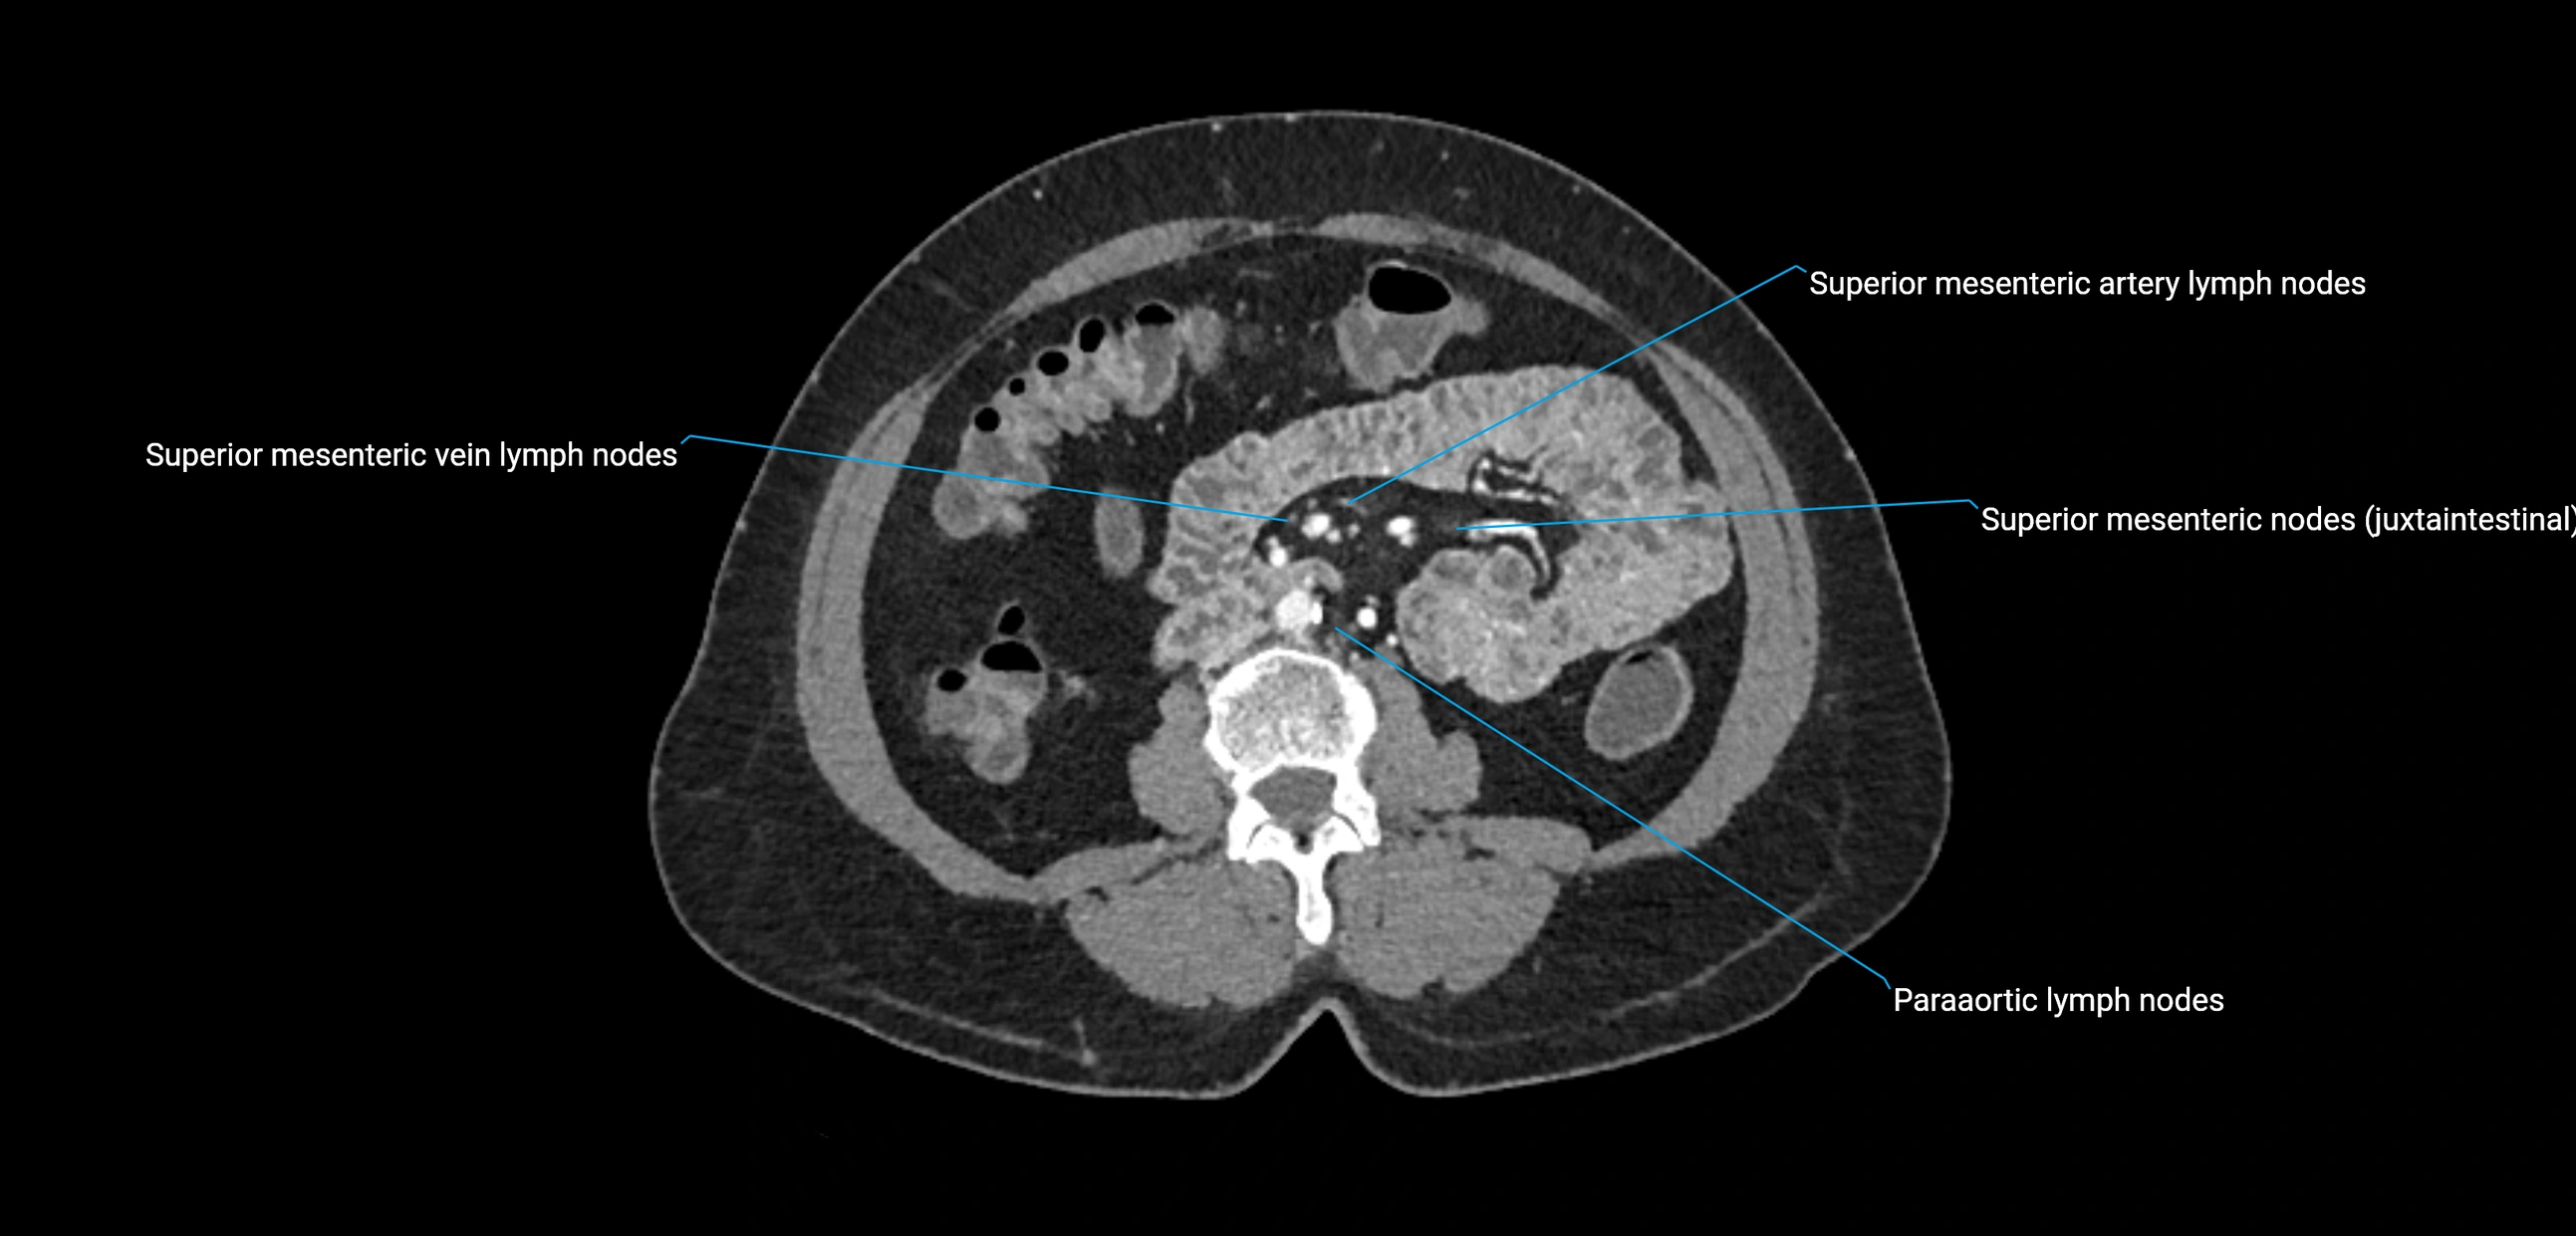

CT Appearance

CT Pre-Contrast:

• Nodes appear as soft-tissue density nodules adjacent to the aorta and IVC

• Calcification may be seen in chronic infections (e.g., tuberculosis)

CT Post-Contrast:

• Normal nodes enhance homogeneously

• Malignant nodes may show heterogeneous enhancement, central necrosis, or conglomerate formation

• Size >1 cm short axis is suspicious, though morphology and distribution are equally important